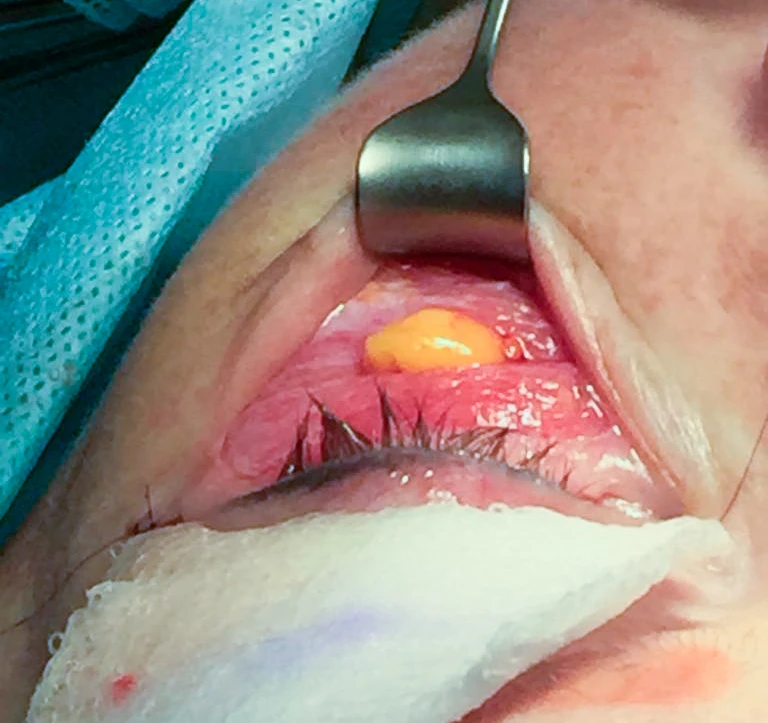

Лазерным лучом аппарата SmartXide2 DOT (фракционный лазер CO2) при использовании импульса DekaPulse (D-Pulse) с параметрами power 5.0 * 5 Гц был выполнен разрез (хирургической насадкой) кожи нижнего века от слезной точки, далее на расстоянии 2 мм от реснитчатого края до наружного угла глаза (на 0,5–1,0 см за наружный угол глаза) по средней борозде «гусиной лапки». Однослойный кожный лоскут в области нижнего века бережно отслаивался до необходимых границ, а именно до малярного жирового пакета, с полным сохранением сосудистой сетки (рис. 2а).

Лазерным лучом были рассечены подкожные связки носослезной борозды. На круговой мышце глаза был выполнен перфорационный тонкий тоннель над подглазничным жировым пакетом. Излишки пролоббированного жира резецированы (рис. 2б).

Пролоббированная часть подглазничного жирового пакета до резекции

Рис. 2б. Пролоббированная часть подглазничного жирового пакета до резекции